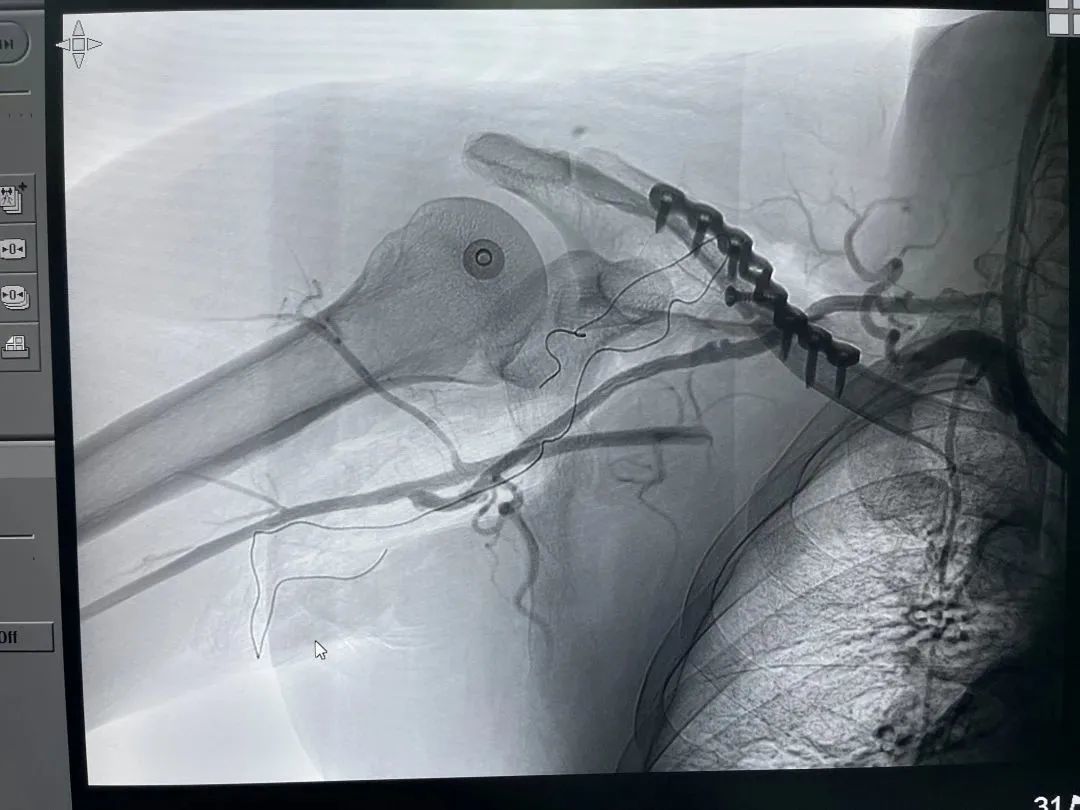

血管接通影像学

6月30日上午,手术在数字化复合杂交手术室进行,周围血管科袁会军主任局麻下微创安置血管球囊,并例行造影检查双侧颈总动脉供血及颅内血管交通支代偿情况,发现患侧颈总动脉为优势动脉,提示血供阻断时间不能太长,否则术后极易造成颅内缺血,这也为手术吻合提出了更高的要求,球囊放置结束后即由麻醉科王仿主任和李璐医师实行全身麻醉,手术麻醉一科李水霞护士长积极配合,各项准备工作有条不紊。

宋涛主任沉着冷静,快速分离,半小时内完成了血管端侧吻合,通血后看到大隐静脉远端出血通畅,所有人都长长地松了口气,然而紧张的工作并没有结束,手术继续探查臂丛神经,见连续性完整,随后复位锁骨骨折,用钢板及螺钉予以固定。将大隐静脉穿过锁骨下通道,与腋动脉行端-侧吻合,恢复血供后见移植搭桥的大隐静脉及腋动脉通血与搏动良好,尺桡动脉搏动恢复。手术历时10个小时,患者全麻复苏后生命体征一切平稳,右手也恢复了正常的温度。